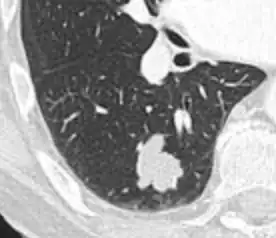

• Margin morphology: a spiculated margin is a risk factor for cancer.[8] Benign causes tend to have a well defined border, whereas lobulated lesions or those with an irregular margin extending into the neighbouring tissue tend to be malignant.[10] In particular, spiculations are highly predictive of malignancy with a positive predictive value up to 90%.[9] Also, a "notch sign", which is an abrupt indentation of the nodule, increases the risk of cancer, but may also be found in granulomatous diseases.[9]

Calcifications and popcorn-like appearance, conferring a diagnosis of hamartoma.[9]

• In case of calcifications, a popcorn-like appearance indicates a hamartoma, which is benign.[3]